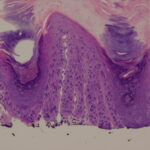

Histopathology

Actinic keratoses are keratinocytic dysplasias or squamous cell carcinomas in situ. This definition is preferable to their designation as precancerous because most of them never progress to cancers. Biologically, the lesions are still benign; invasion into the dermis, if present at all, is limited to the most superficial portion, the papillary dermis (see Differential Diagnosis) . |

This variety of keratosis, sometimes referred to as florid keratosis, may easily be overdiagnosed as invasive squamous cell carcinoma by the unwary. Mild or moderate papillomatosis may be present. The epidermis is thickened in most areas and shows irregular downward proliferation that is limited to the uppermost dermis and does not represent frank invasion .A varying proportion of the keratinocytes in the stratum malpighii show a loss of polarity and thus a disorderly arrangement. Some of these cells show pleomorphism and atypicality (“anaplasia”) of their nuclei, which appear large, irregular, and hyperchromatic. Often the nuclei in the basal layer are closely crowded together. Some of the cells in the midportion of the epidermis show premature keratinization, resulting in dyskeratotic cells or apoptotic bodies characterized by homogeneous, eosinophilic cytoplasm with or without a nucleus. In contrast to the epidermal keratinocytes, the cells of the hair follicles and eccrine ducts that penetrate the epidermis within actinic keratoses retain their normal appearance and keratinize normally. Occasionally, cells of the normal adnexal epithelium extend over the atypical cells of the epidermis in an umbrella-like fashion. In some cases, abnormal keratinocytes extend downward on the outside of the follicular infundibulum to the level of the sebaceous duct and, less commonly, along the eccrine duct . |